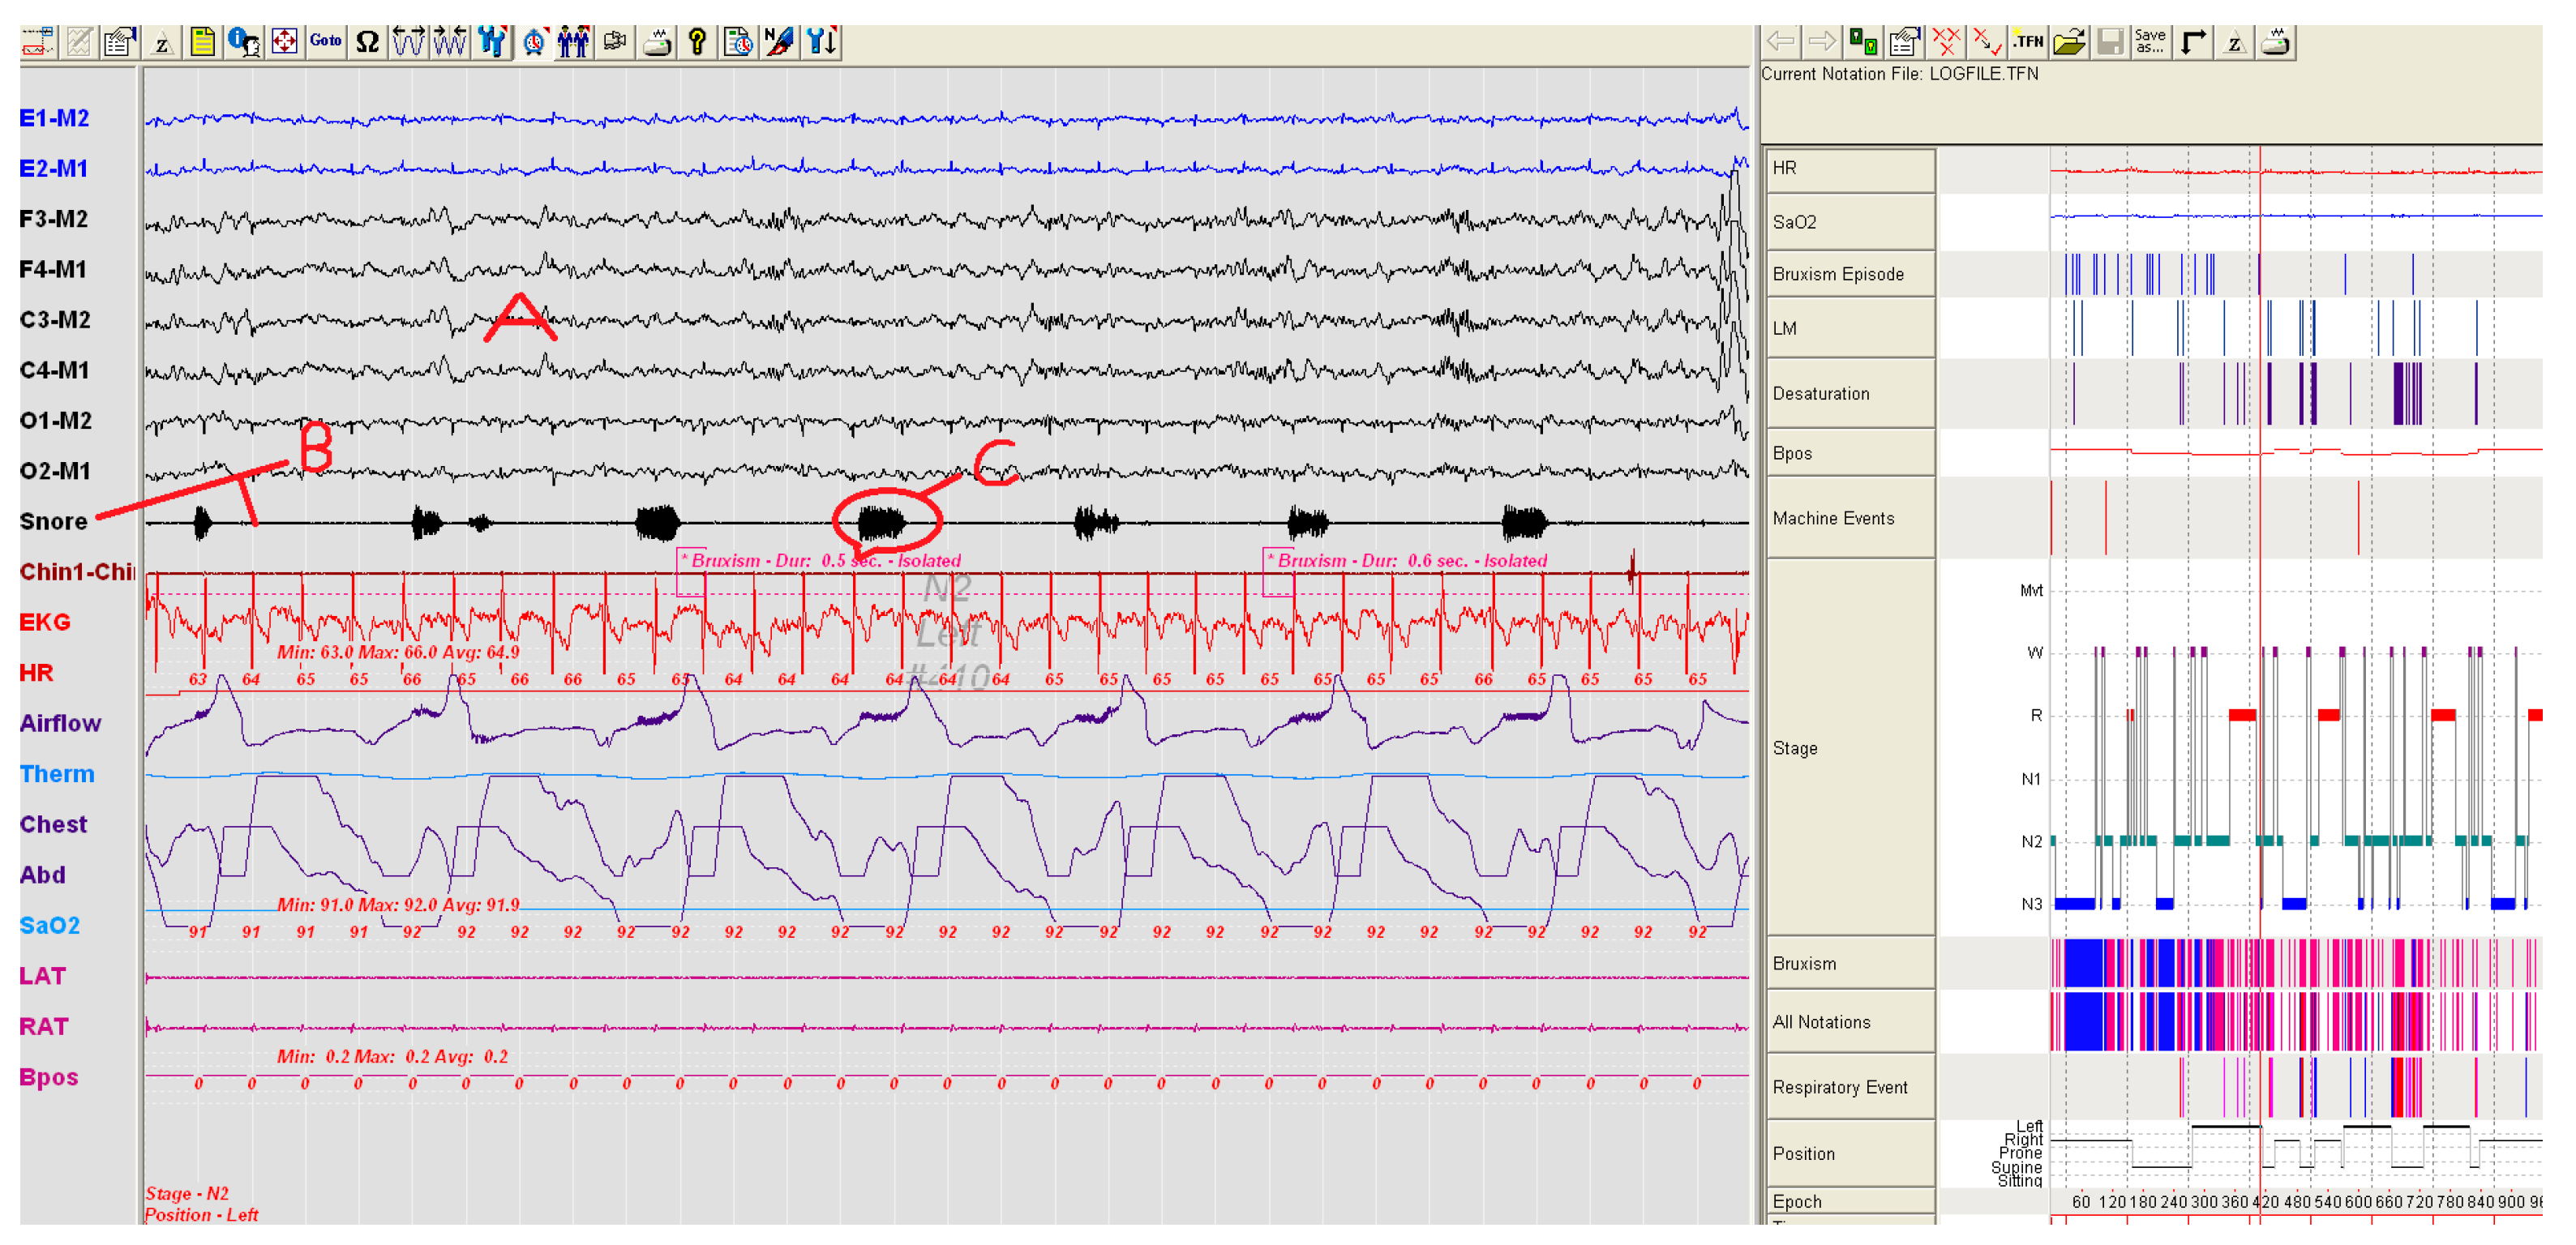

Using the PSG, the number and severity of snoring for each patient were compared. Snoring severity and number of the group using SNORAP were found to be statistically lower (Paired Sample Test, p < 0.05) than when compared to the group not using SNORAP. A volunteer patient from study groups in Figure 7 and Figure 8 was shown a sample PSG recording before and after using SNORAP. 6-channel EEG (A) and snoring trace (B) are given in Figure 7. The high amplitude snoring packets (C) are seen in the snoring trace in Figure 7. Figure 8 shows the PSG recording of the same volunteer patient when the SNORAP was applied to that patient. When his snoring trace in these conditions is reviewed, it is seen that the high amplitude snoring packets are completely removed. No wave of being awake was observed in his sleep EEG.

Figure 7.

A patient sample not using SNORAP—high volume snoring sounds are observed in the snore line (A: 6-channel EEG, B: Snoring trace, C: high amplitude snoring packets).